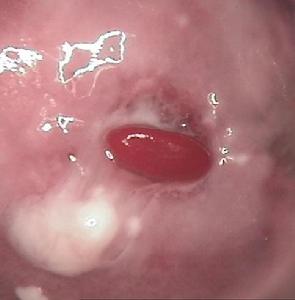

正在流血的宫颈息肉宫颈息肉可发生于任何年龄,宫颈息肉虽为比较常见的妇科疾病,但由于其体积小,可无任何症状,往往因患其它妇科疾病检查时才被发现。较大的息肉可能出现白带增多,或主诉有接触性出血,特别在性交或排便后出现点滴状出血或血性白带,出血量一般不多。表面被覆鳞状上皮的息肉,由于其质地较韧,一般无接触性出血或血性白带。如宫颈息肉伴有较重的宫颈炎,也可出现宫颈炎的症状。

宫颈息肉的阴道镜所见:根据宫颈息肉表面被覆的上皮不同,阴道镜下有2种图像。属宫颈管粘膜过度增生堆集而形成者,阴道镜下息肉呈鲜红色,有一定光泽,单发者有一较细的蒂,多发者呈簇状,基底较宽,蒂较短。涂3%醋酸后表面可见水肿之柱状上皮,但不像糜烂出现“葡萄串”改变。整个息肉表面似有一层极薄的包膜,反光性好。起源于宫颈阴道部表面被覆鳞状上皮的息肉,息肉为粉红色,从宫颈鳞状上皮区突出,基底较宽,也有少数有一较细的蒂,质地较韧,涂3%醋酸后上皮略呈白色改变,数秒钟后即恢复原状。前者较软,质脆,触之易出血,后者较硬,不易出血。 医学百科网 | YxBaike.Com